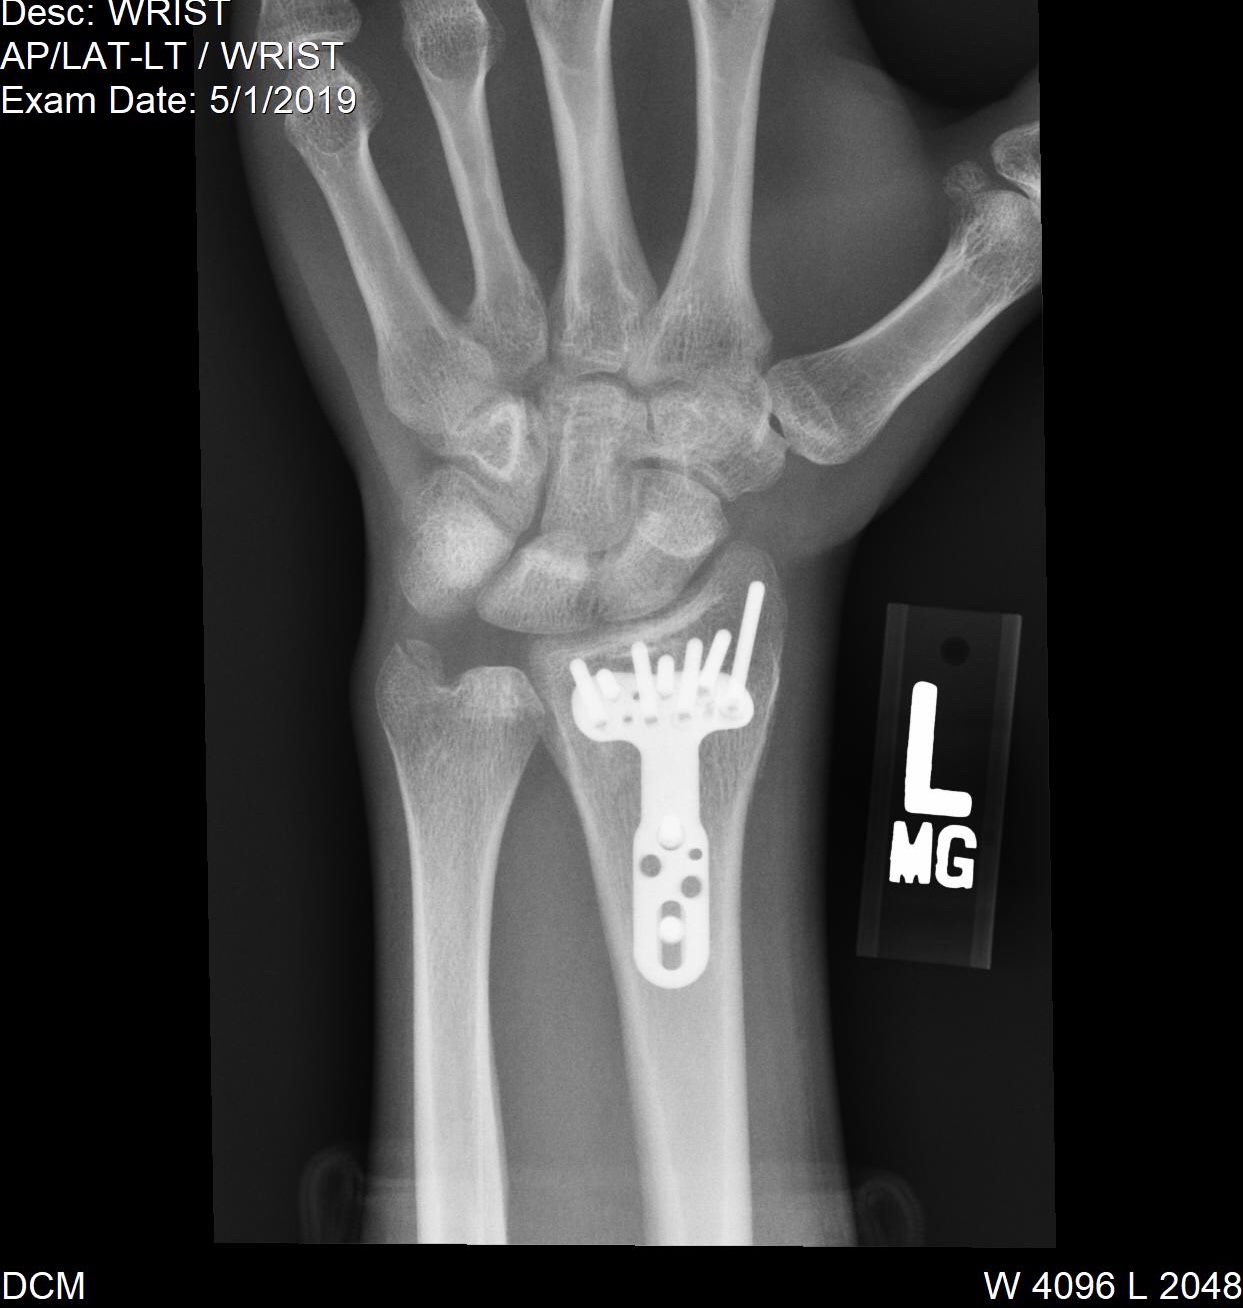

Platte aus handgelenk entfernen wie lange krank. Bevor das Material entfernt werden kann muss der knöcherne Heilungsprozess vollständig abgeschlossen sein dies kann der Arzt auf dem Röntgenbild erkennen. 10 Tagen werden die Wundfäden entfernt. Die Heilungszeit des Knochens und der Weichteile beträgt allerdings in den meisten Fällen mindestens 3 4 Monate gelegentlich auch über 6 Monate bis Vollbelastung möglich ist.

Kommt es durch voluminöse Platten durch vorstehende Schraubenköpfe oder überlange Schrauben zu einer direkten Sehnenschädigung oder durch eine Fehllage der Schrauben zu einer Behinderung der Gelenkbeweglichkeit muss das gesamte Material vorzeitig entfernt werden. 2 wochen krankschreiben würde wenn er sich seine platten und schrauben die er so im körper hat entfernen lassen würde. Versuchen alles sofort wieder zu bewegen.

Ich hab meine Platte im Handgelenk auch nach 8 Monaten entfernen lassen raus mit dem Fremdkörper. Die Entfernung des Metalls stellt einen kleinen Eingriff dar als der der bei der ursprünglichen Operation notwendig war.

Distale Radius Fraktur Platte Schrauben Rontgenbild Gesundheit Und Medizin Gesundheit Operation